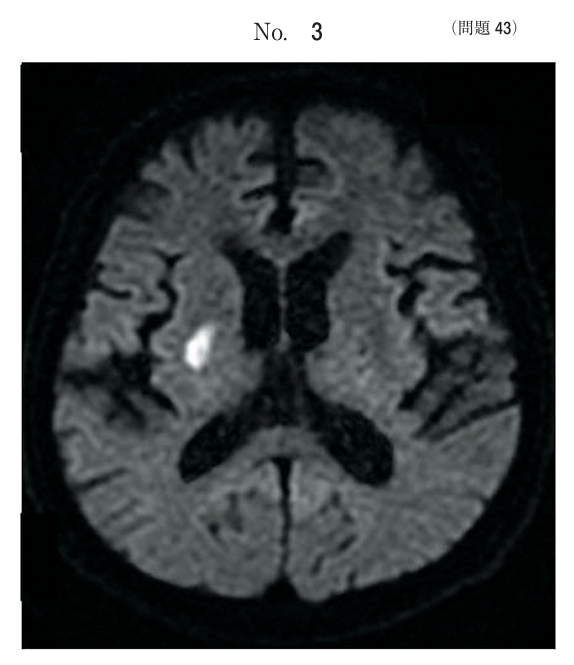

午前/問題43

発症2時間後の右基底核梗塞のMR像において、画像の種類はどれか。

1.FLAIR像

2.T1強調像

3.T2強調像

4.拡散強調像

5.プロトン密度像